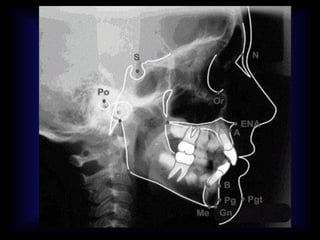

PUNTOS CRANEOMÉTRICOS:

PUNTOS CEFALOMÉTRICOS:

• S:Sella: centro geométrico de la silla turca en al punto medio de su concavidad.

• A:punto mas profundo de la concavidad anterior del hueso maxilar.

• N: Nasion: punto de unión entre las suturas Internasal y frontonasal Sutura

Frontonasal

• B:punto más posterior de la concavidad anterior del hueso mandibular

• O: Oregón, punto inferior de la orbita

• SNA: la espina nasal anterior

PUNTOS CRANEALES ANATÓMICOS

UNILATERALES:

• Silla (S)

• Basión (Ba)

• Nasión (N)

• Silla: (s) Silla Turca

• Basión: (Ba) Punto medio en el borde

anterior del forámen magno

• Nasion: (N) Punto de encuentro de las

suturas internasal y nasofrontal

BILATERALES:

• Porión (Po)

• Bolton (Bo)

• Articulare (Ar)

PUNTOS FACIALES ANATÓMICOS

 Punto A

 Espina nasal anterior (ENA)

 Espina nasal posterior (ENP)

 Prostión (Pr)

 Infradental (Id)

 Pogonión (Pog)

 Gnatión (Gn)

 Mentoniano (Me)

 Punto B

• Punto A : punto de mayor conceavidad entre la espina nasal y

prostion

• Punto B: Punto de mayor concavidad entre el infradental y el

pogonion

• ENA, ENP

• Pogonión (Pog) Punto más anterior de la protuberancia

mentoniana

• Orbitario (O)

• Ormafrom(Omr)

• Condileón (Co)

• Eje condilar (Dc)

• Gonión (Go)